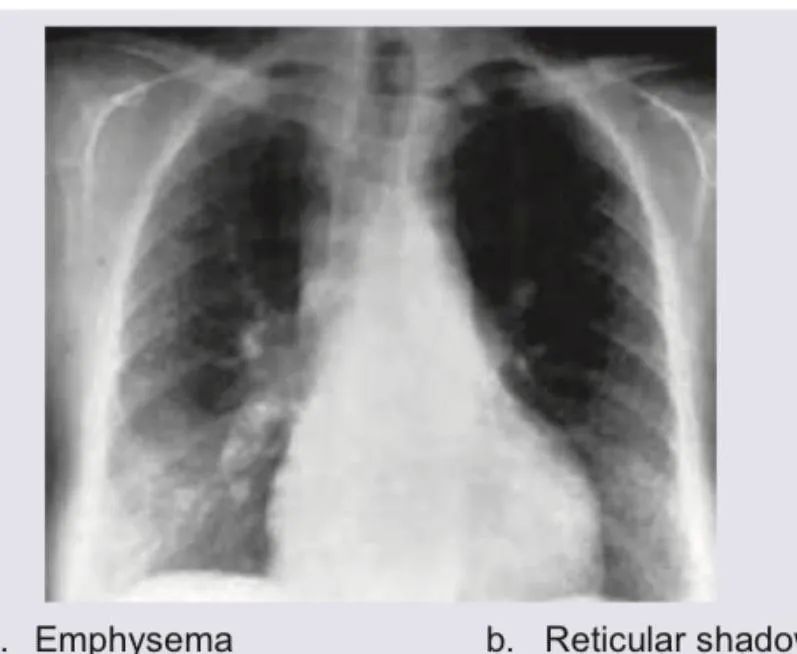

Visual Aid